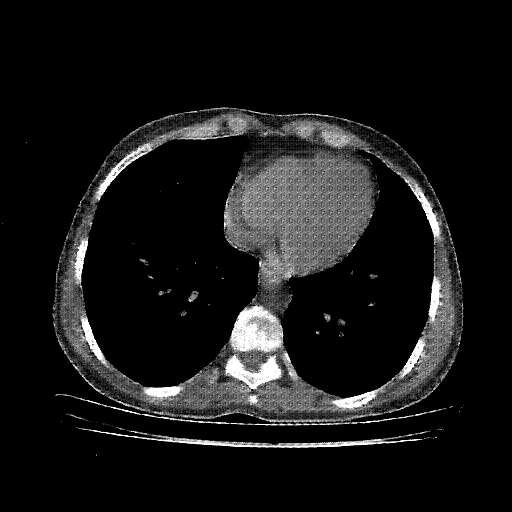

Generated VENOUS CT scan (A→B translation)

Full window (WL 1023.5, WW 4095 β†’ Low βˆ’1024, High +3071)

Actual HU range: [-1024.0, 959.4]